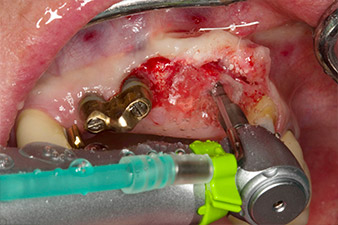

Following primary healing, the soft tissues were shaped using the basally lined bridge. Two months later the site was exposed by a slightly palatal alveolar ridge incision (Fig 2). The dimensions of the alveolar bone proved to be sufficient at position 22. Figures 2 and 4 show the preparation of the implant bed, the tapping and the implantation using Implantmed.